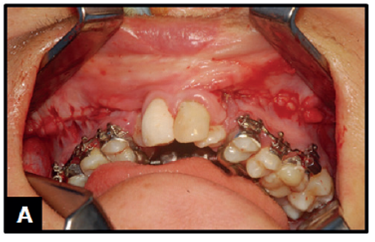

No que segue é descrita a ERMAC em um paciente com FBCLP (Figura 1). A técnica foi realizada com o indivíduo em decúbito dorsal horizontal, sob anestesia geral, intubação nasotraqueal, mediante antissepsia intra e extrabucal com polivinilpirrolidona-iodo degermante e tópico com 10% de iodo ativo. Em continuidade, procedeu-se então à infiltração com solução de xilocaína a 2% contendo vasoconstritor no fundo de sulco da maxila (Figura 1B). Após, foi prontamente efetuada incisão mucoperiosteal (Figura 1C) bilateral localizada 3 a 5 mm acima da união mucogengival, seguida por descolamento tecidual (Figura 1D), partindo-se da região da abertura piriforme até a tuberosidade da maxila; nesta situação concomitante com a exposição do nervo infraorbitário bilateralmente.

A) Indivíduo de 22 anos de idade, gênero masculino, pardo, com FBCLP, submetido quando criança à queiloplastia e palatoplastia, sem intervenção nos defeitos ósseos alveolares, preparado para a cirurgia de ERMAC. Observa-se atresia maxilar combinada com deficiências nos sentidos transversal e ântero-posterior; B) Infiltração com solução de xilocaína a 2% contendo vasoconstritor; C) Incisão mucoperiosteal; D) Descolamento do retalho.

Figura 1: A) Indivíduo de 22 anos de idade, gênero masculino, pardo, com FBCLP, submetido quando criança à queiloplastia e palatoplastia, sem intervenção nos defeitos ósseos alveolares, preparado para a cirurgia de ERMAC. Observa-se atresia maxilar combinada com deficiências nos sentidos transversal e ântero-posterior; B) Infiltração com solução de xilocaína a 2% contendo vasoconstritor; C) Incisão mucoperiosteal; D) Descolamento do retalho.

Fonte: Documento obtido durante o estudo.